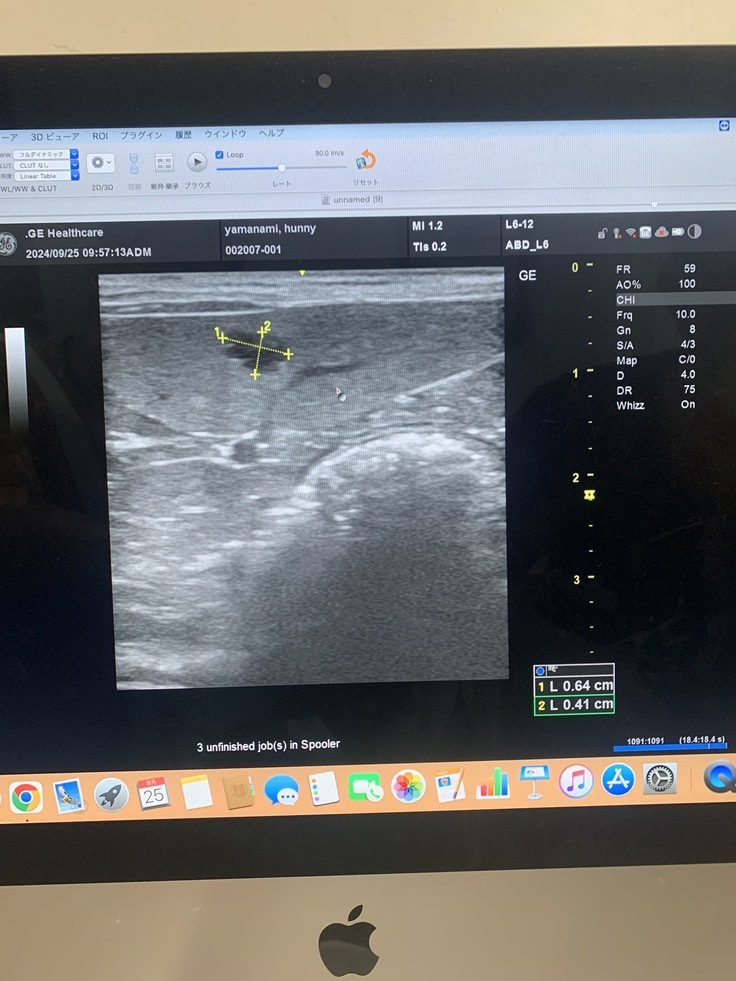

脾臓にしこり、影→1センチ4ヶ所が見つかった